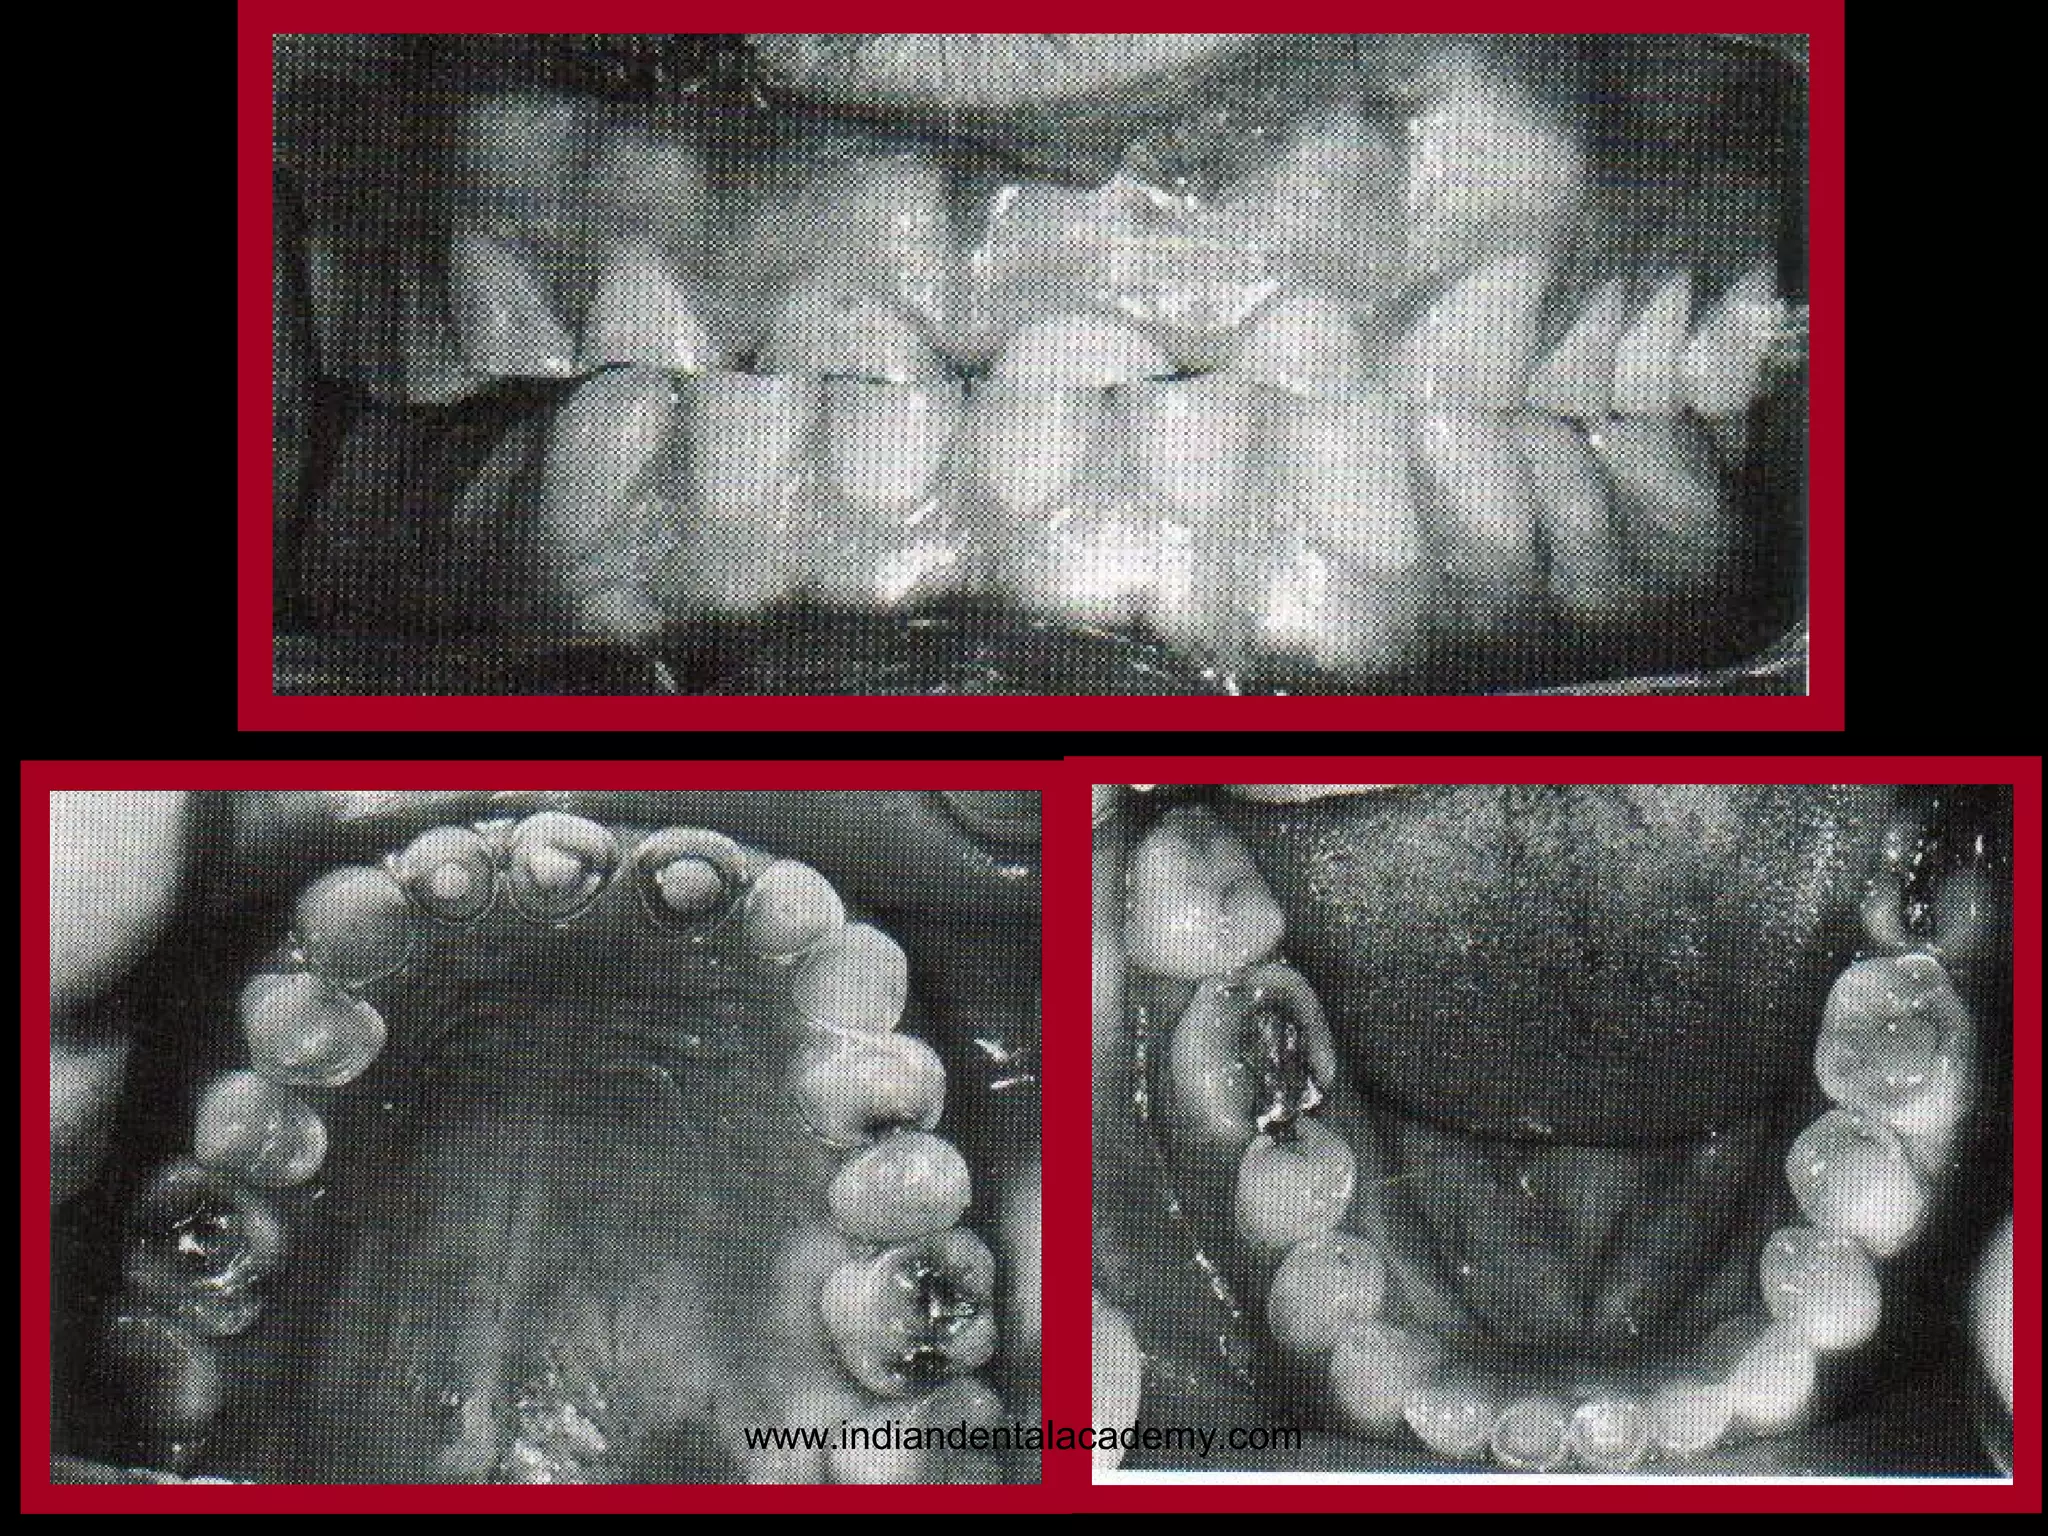

BRUXISM.

Sustained grinding, rubbing

together, or gnashing of the teeth

with greater-than-normal chewing

force is known as bruxism.

This activity may be diurnal,

nocturnal, or both.

Although bruxism is initiated on a

subconscious level, nocturnal

bruxism is potentially more harmful

because the patient is not aware of it

while sleeping.

www.indiandentalacademy.com

102

103

It is common for wear on anterior

teeth to progress from initial faceting

on the canines to the central and

lateral incisors.

Once vertical overlap diminishes as

the result of wear, posterior wear

facets are commonly observed.

However, the chewing patterns of

normal subjects can be quite varied,

and the relationship, if any, between

altered mastication and occlusal

dysfunction is not clear.